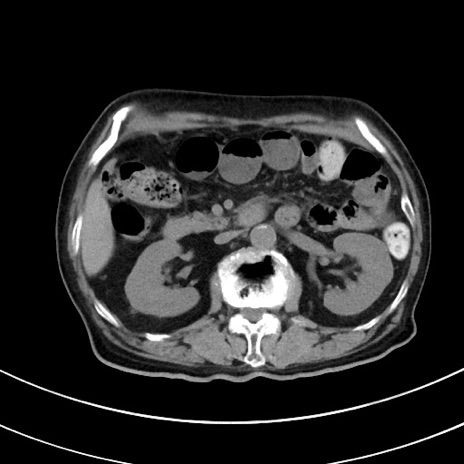

症例33(横断像)

【症例】70歳代 女性

【主訴】心窩部痛

【現病歴】延髄病変の精査・加療にて神経内科入院中。本日より心窩部痛あり。

【既往歴】虫垂炎

【身体所見】右下腹部を中心に圧痛と反跳痛あり。

【データ】WBC 10900、CRP 0.02